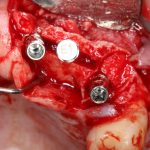

Вот клиническая картина через 4 месяца после ранее проведенной имплантации с остеопластикой:

Как видишь, коллеги из недалекой дружественной страны не осилили снятие швов. Мне это не нравится, хотя и объясняет, почему люди готовы ехать за тыщи километров ради 20-минутной операции удаления зуба мудрости.

Ну хорошо. Швы сняли. Делаем разрез. Обрати внимание, что после всех проведенных операций у нас остается очень небольшой по ширине слой жевательной слизистой оболочки:

Устанавливаем формирователи десневой манжеты. Сегодня я называю эту процедуру не менее важной, чем любой другой этап имплантологического лечения: